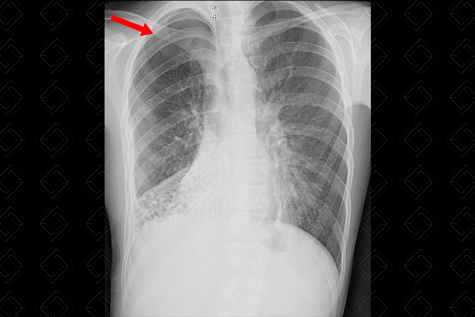

Descrição das figuras 1 e 2: Paciente em tratamento hospitalar de pneumonia comunitária complicada com derrame pleural. Apresenta piora clínica e laboratorial, com o padrão radiológico mantido na radiografia de tórax. Optou-se por realizar tomografia do tórax com contraste venoso para avaliar complicações.

Na tomografia, observamos a presença do dreno pleural (figura 1) adjacente à consolidação. Como complicação, observa-se pneumotórax à direita (asterisco - figura 2) e enfisema de partes moles ipsilateral (setas vermelhas - figura 2).